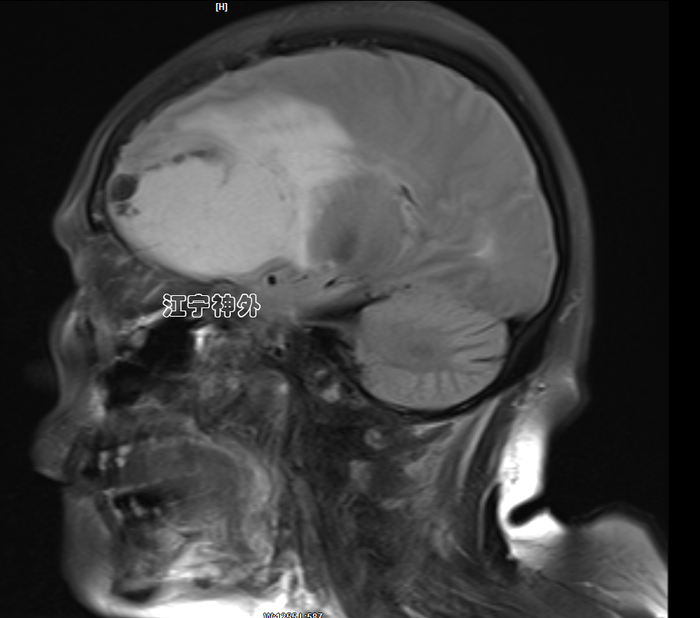

术后一周复查磁共振,显示肿瘤完全切除,脑组织水肿仍比较明显,继续用药。术后两周拆线出院,切口愈合良好,无任何并发症。术后病理提示脑膜瘤。